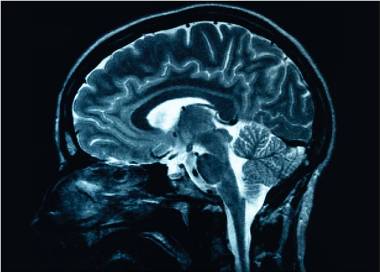

Boala Alzheimer este asociată în mod tradițional cu vârsta înaintată, însă până la 10% din toate cazurile diagnosticate pot fi de debut precoce, adică la pacienți cu vârsta sub 65 de ani. Examenele medicale au relevat o micșorare a hipocampului, partea creierului responsabilă de memorie, iar în lichidul cefalorahidian au fost identificați biomarkeri caracteristici bolii Alzheimer. Acest caz unic sugerează că dezvoltarea bolii Alzheimer poate fi un proces mai complex decât se credea anterior.